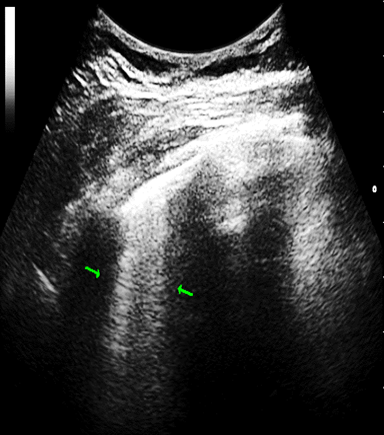

The B-line was defined as a coherent, wedge-shaped or triangular echogenic signal with a narrow beginning near the edge of the image at the pleural line extending longitudinally by the pulmonary parenchyma to the edge of the image (Figure 1).3,21

Figure 1 B-lines: vertical and perpendicular to the pleural echo, starting from it with comet tail. appearance. 2 B-lines (arows) in patient with systemic sclerosis (Author’s own imsage).

2 B-lines (arows) in patient with systemic sclerosis (Author’s own imsage).